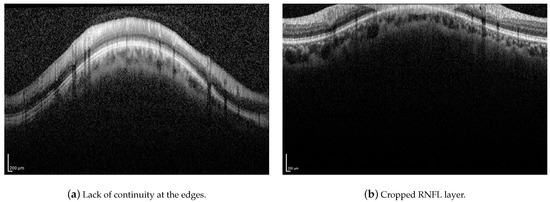

Although the proposed method has proven to be robust to image artifacts produced by vessels shadowing and speckle noise of usual practical scenarios (variance less than 0.1), some issues may hinder the correct segmentation of the RNFL. Neither the proposed method nor the H-DLpNet method do not provide satisfactory results in four images of the dataset, in which the retinal layers suffer from the lack of continuity at the edges of the image or where part of the RNFL is cut off in the image area, as exemplified in Figure 19. It should be noted, however, that in clinical practice, the expert repeats the acquisition of such images, as they are considered invalid.

Figure 19.

Examples of challenging images for the application of the proposed method.